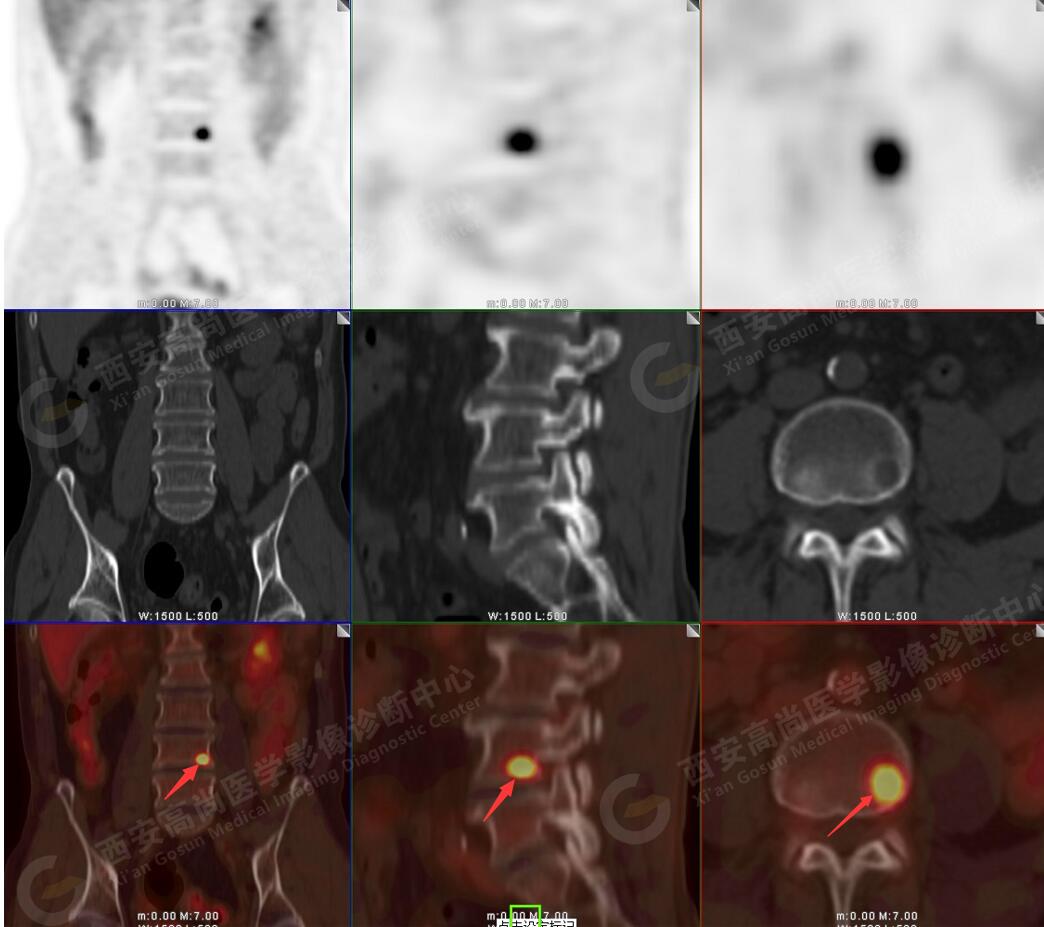

2.以下為全身多發(fā)轉(zhuǎn)移灶

5.腰4椎體左側(cè)緣溶骨性骨質(zhì)破壞,F(xiàn)DG代謝異常增高,考慮骨轉(zhuǎn)移瘤。